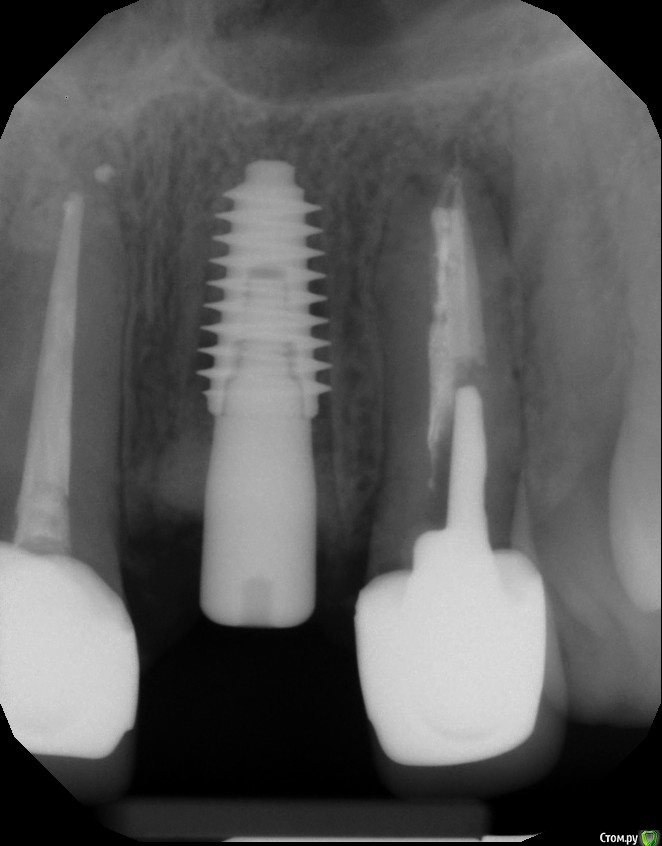

almaz7888 Опубликовано 28 января, 2021 Поделиться Опубликовано 28 января, 2021 Доброе утро коллеги! Планирую одномоментную имплантацию в область 2.1 зуба ( AnyRidge 3.5*11.5). В области апекса костный дефект. Думаю заполнить ксенографтом и перекрыть резорбируемой мембраной 1.5*2.0. Думал насчет спейсера Стоит ли такой имплант сразу нагрузить? или же лучше сделать адгезивный мост. Ссылка на комментарий

Astronaft Опубликовано 29 января, 2021 Поделиться Опубликовано 29 января, 2021 Я в похожей ситуации взял 4.5мм диаметр, БиоОсс и СТ трансплантат.AnyRidge тот который имеет сердцевину 3.5мм и глубокую агрессивную резьбу - очень хорошо врезается, риск лизиса кости меньше за счет места между витками. 2 Ссылка на комментарий

almaz7888 Опубликовано 31 января, 2021 Автор Поделиться Опубликовано 31 января, 2021 Я в похожей ситуации взял 4.5мм диаметр, БиоОсс и СТ трансплантат.AnyRidge тот который имеет сердцевину 3.5мм и глубокую агрессивную резьбу - очень хорошо врезается, риск лизиса кости меньше за счет места между витками.Спасибо за совет. Такой имплант по лунке лучше встанет, постараюсь взять больший диаметр, чем предполагал ) Ссылка на комментарий